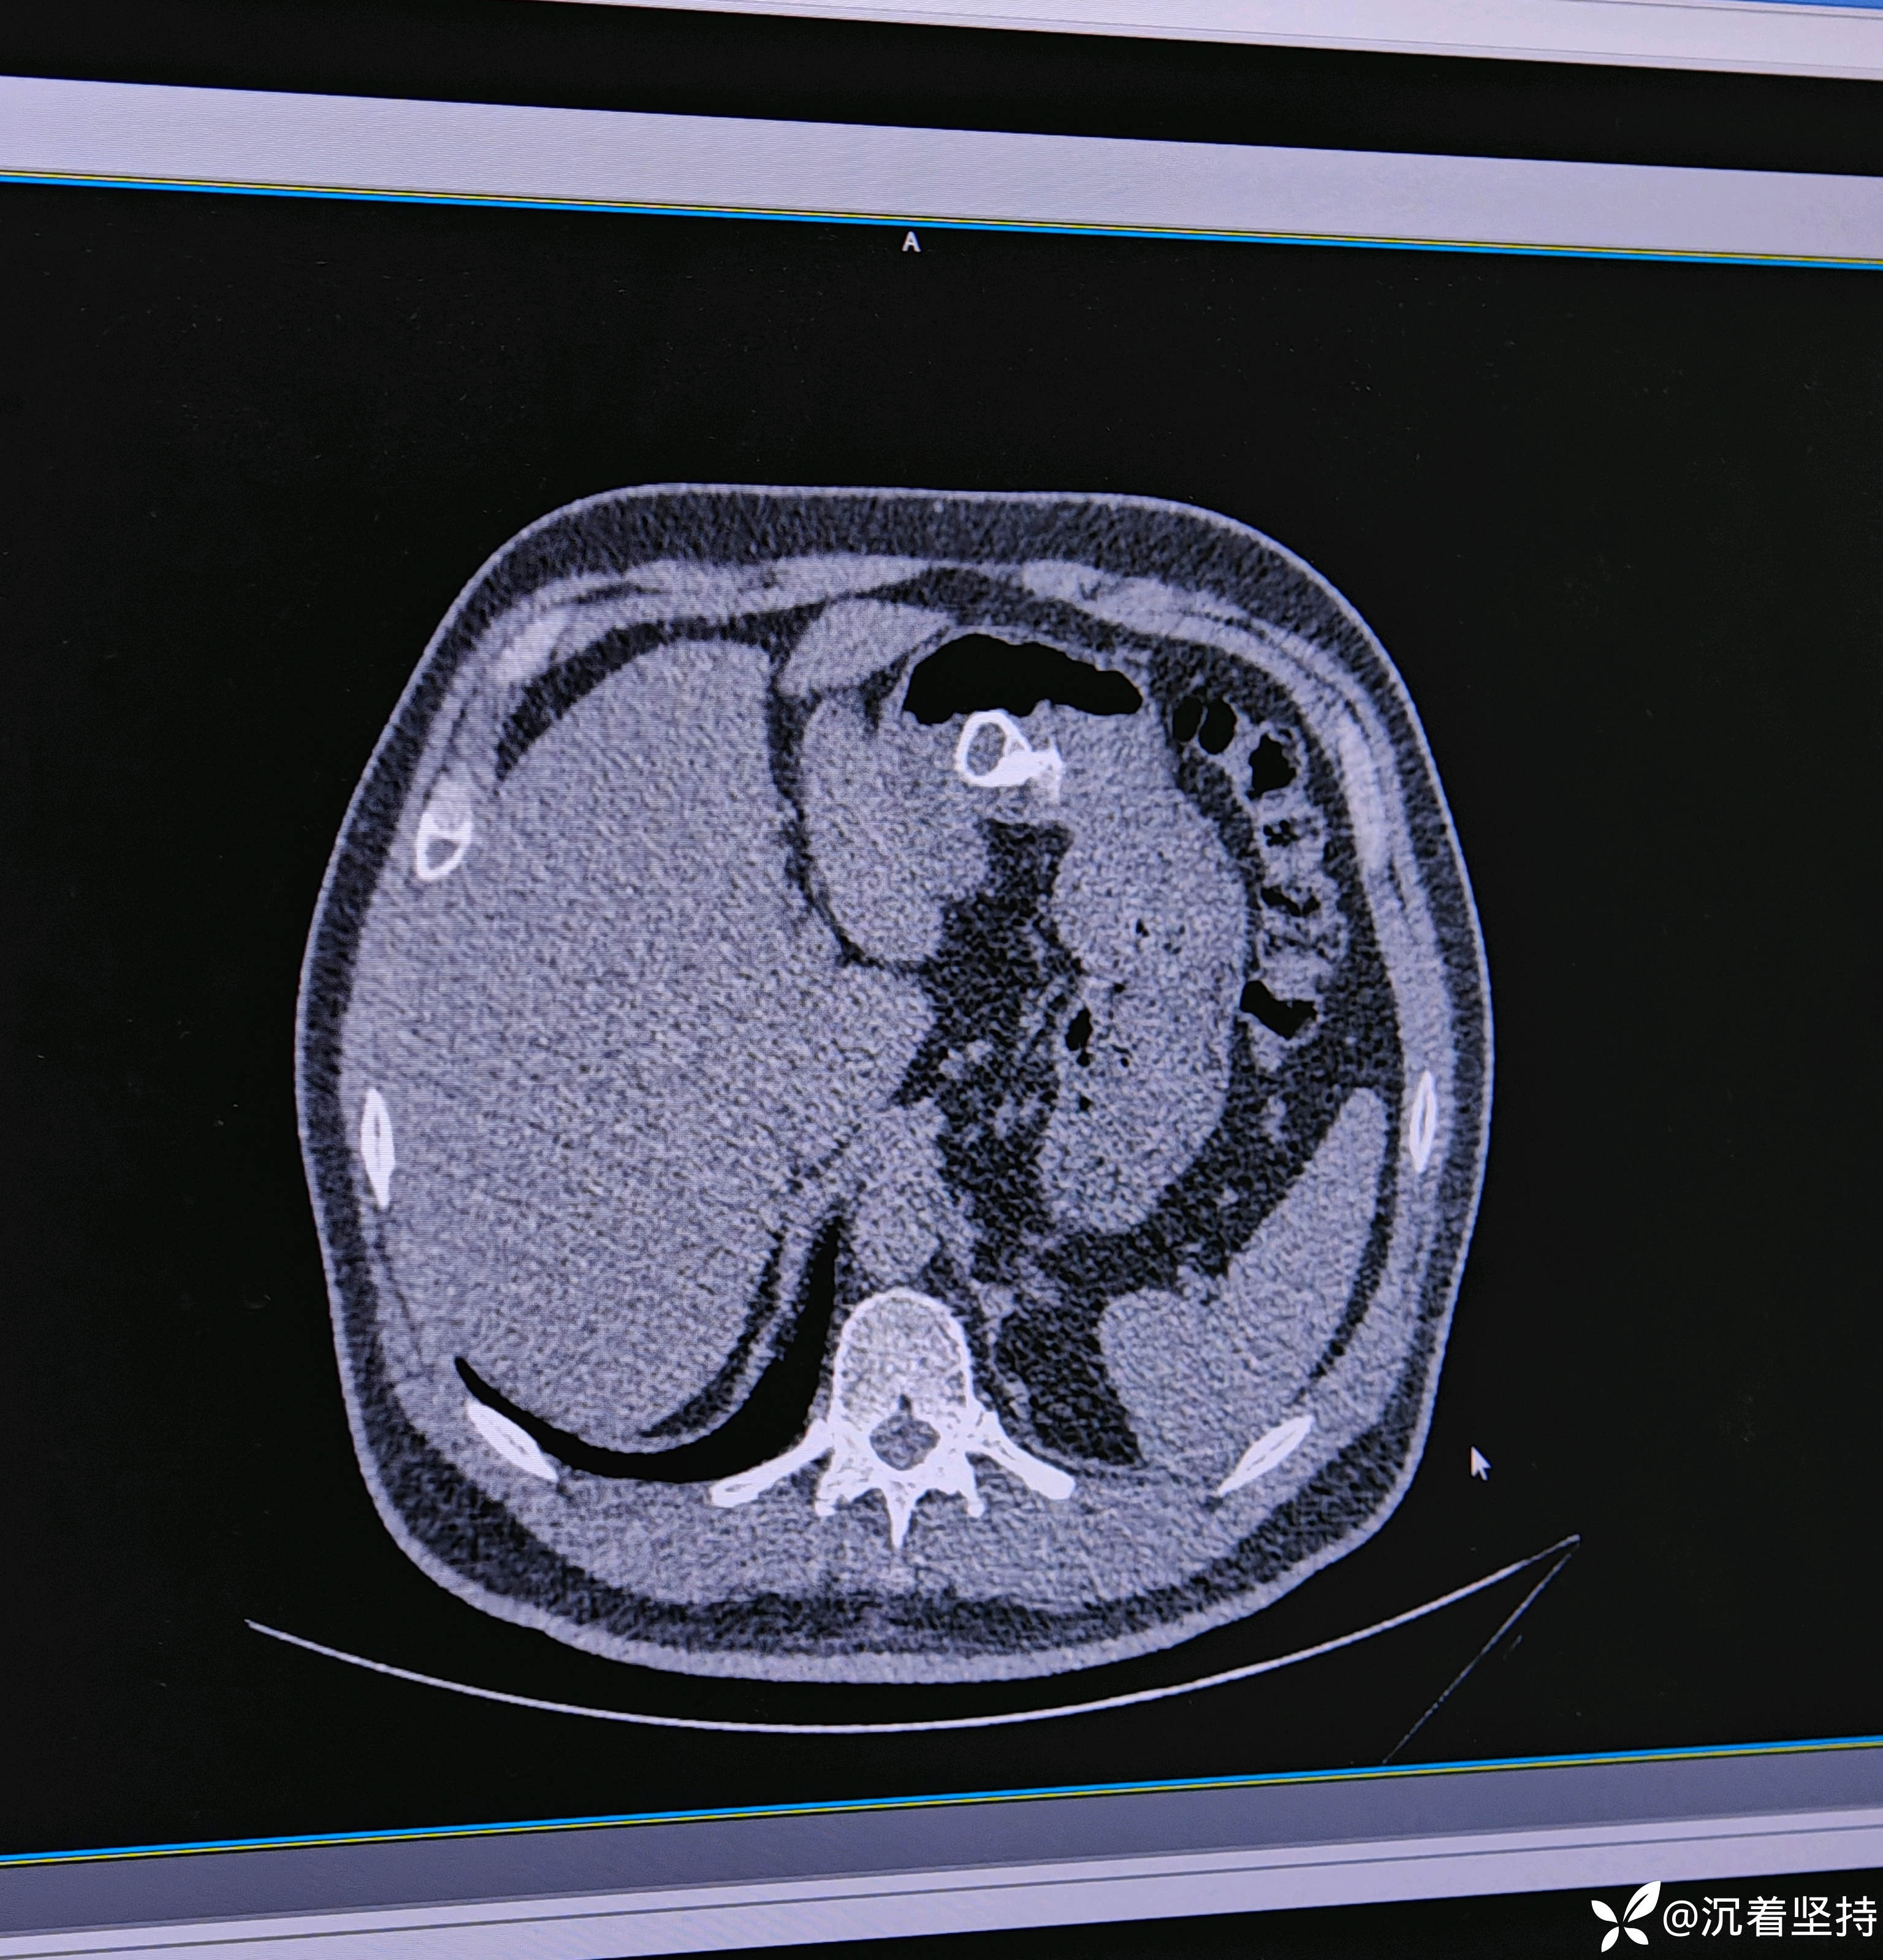

男性,饮酒,不慎喝下😂😓😓